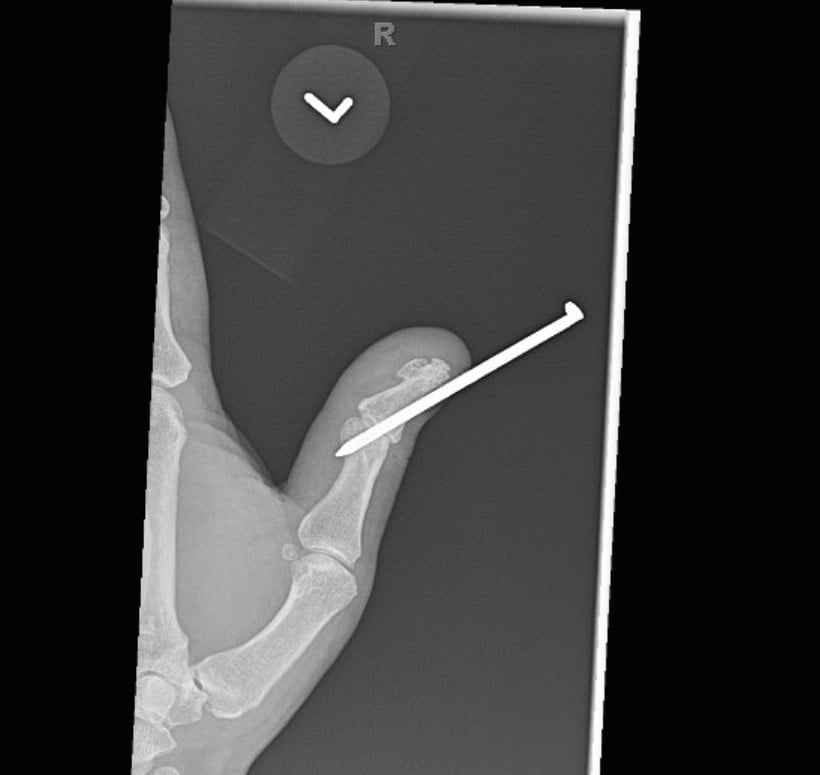

Radiographs were obtained including anterior-posterior and lateral views of the left thumb which demonstrated a penetrating injury of a metallic object (in this case, the threaded nail). The nail on X-ray did appear to pierce the base of the distal phalanx with extension through the interphalangeal joint into the thumb proximal phalanx with an associated vertically oriented split fracture of the proximal phalanx, evident with increased radiolucency on these films. No gas within the soft tissues or other identified foreign bodies; fractures, dislocation, or other acute bony abnormalities were noted. The hospital site has an orthopedic surgery residency program, and the orthopedic surgery resident was consulted given the bony involvement and the recommended outpatient management with an orthopedic hand surgeon.

Post-foreign body removal with cast application X-rays were obtained which redemonstrated the vertically oriented, longitudinal fracture of the left thumb proximal phalanx extending into the interphalangeal joint. Removal of the foreign metal nail also allowed for appreciation of an intra-articular fracture at the distal ulnar aspect of the proximal phalanx where the metallic nail had been previously located, and a distal phalanx base fracture as well. No retained metallic foreign bodies were identified. Of note, there was no involvement of the metacarpal phalangeal joint of the thumb, making this an isolated injury involving only a single joint of the thumb.